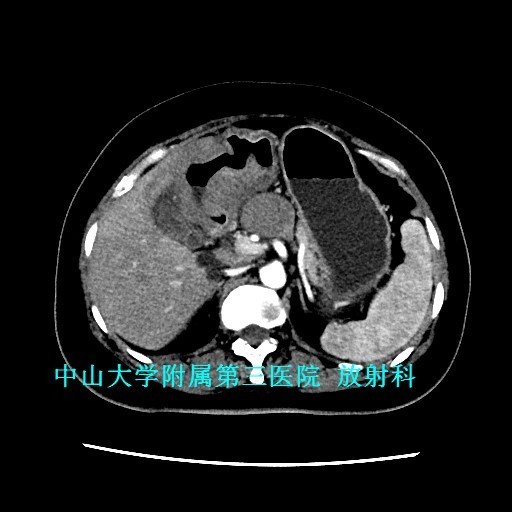

查体:腹软,上腹部轻压痛、无反跳痛,未触及包块。 辅查:1、胃镜:胃十二指肠恶性病变(待病理);2、上腹部CT:胃窦至十二指肠胃壁弥漫性增厚,考虑淋巴瘤可能性大。

讨论:原发性胃肠道淋巴瘤是一组起源于胃肠道黏膜下层淋巴组织的恶性肿瘤,成人较少见,约占胃肠道恶性肿瘤的1~4% 。影像表现具有一定特征性:弥漫性或局限性胃壁增厚是胃淋巴瘤主要特征,增厚的胃壁内缘呈波浪样或分叶状,外缘较光整,胃腔有一定的扩张度,增强扫描动脉期呈轻中度强化,静脉期持续强化。主要与胃癌鉴别,胃癌也表现为胃壁增厚,但一般增厚无淋巴瘤明显,而且胃壁僵硬,官腔变窄,常有浸润周围组织器官。 参考文献:侯明杰,齐鹏飞,高万勤等.原发胃肠道淋巴瘤的影像表现和误诊分析[J].实用放射学杂志,2014,(12):2112-2113,2121.